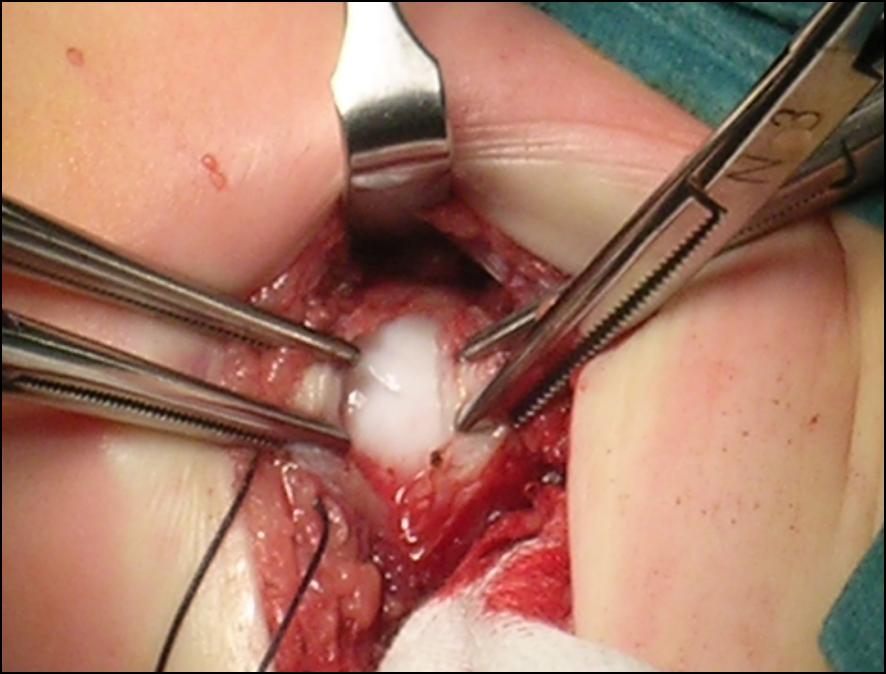

In rari casi, anche con il confezionamento di un gesso, la riduzione non è ottenuta, ad indicare la presenza di ingombri fisici che ne impediscono la riduzione. L’unico modo per ripristinare la congruenza articolare è rimuoverli con un intervento chirurgico mirato. A seguito l’immobilizzazione in gesso permette la formazione di una cicatrice resistente, mantenendo in sede i capi articolari.

In questi casi si ricorre a soluzioni chirurgiche che associano tempi sui tessuti molli e sulle strutture ossee. Vengono per cui presi in considerazione osteotomie femorali o di bacino, acetabuloplastiche per migliorare la continenza acetabolare, tenotomie degli adduttori e ritensionamento capsulare.